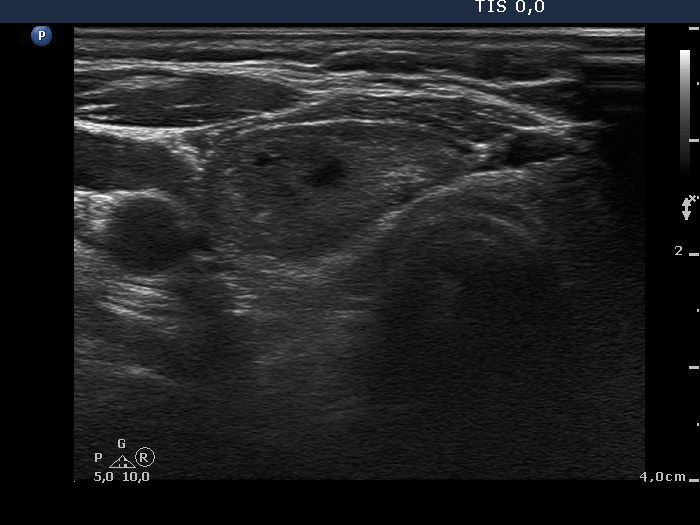

Follicular adenoma - Case 5. |

Clinical data: a 67-year-old woman was referred for an evaluation of a nodule discovered on carotid Doppler examination.

Palpation: a firm nodule in the right lobe.

Ultrasonography: the thyroids were minimally-moderately hypoechogenic. There was a moderately hypoechogenic nodule in the right lobe. The nodule displayed a halo sign and perinodular blood flow.

Cytological diagnosis: follicular tumor. Lymphocytic thyroiditis.

Histopathological diagnosis: microfollicular adenoma. Chronic lymphocytic thyroiditis.